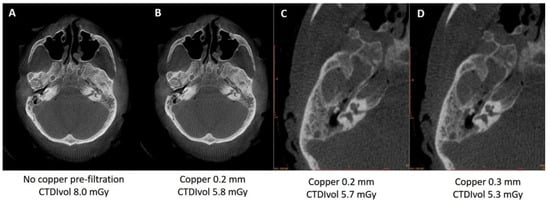

3.2.1. Pre-Filtration with 0.2 vs. 0.3 mm Copper Filter